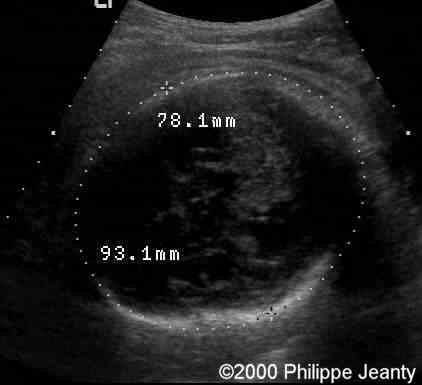

One kidney length was 23 mm (5th percentile: 36mm, mean: 41, 95th percentile: 46mm)

case0020-6a

The other is 29 mm. So both kidneys are just a little above half the normal size ! Surprisingly this was not recognized by many.